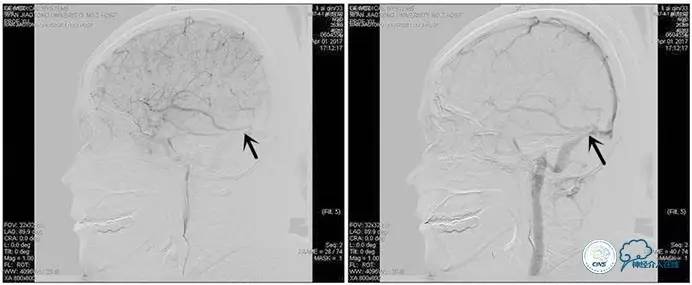

术中造影

5ml/s,总量8ml,压力100~150

手术方案

1、6mm×20mmAviator球囊(Cordis)分段对狭窄部位进行扩张。

2、植入7mm×40mmPrecise自膨支架。